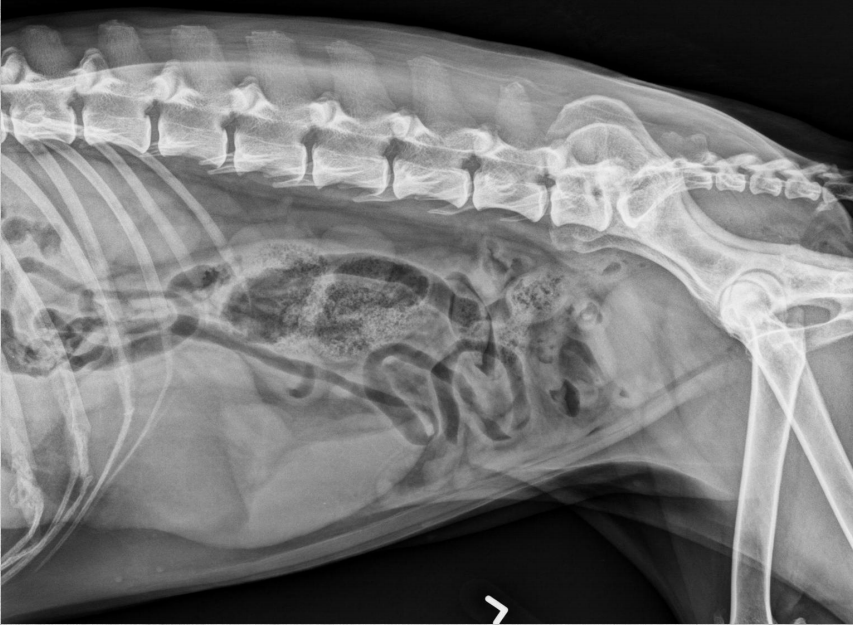

●9 yo female sterilized German

Shepherd

●Anorexia, lethargy

●Weakness

● Mass effect, bowels lifted dorsally

and caudally

● Round shadow cranially to tail of

the spleen

● Splenomegaly, splenic mass. hemangiosarcoma